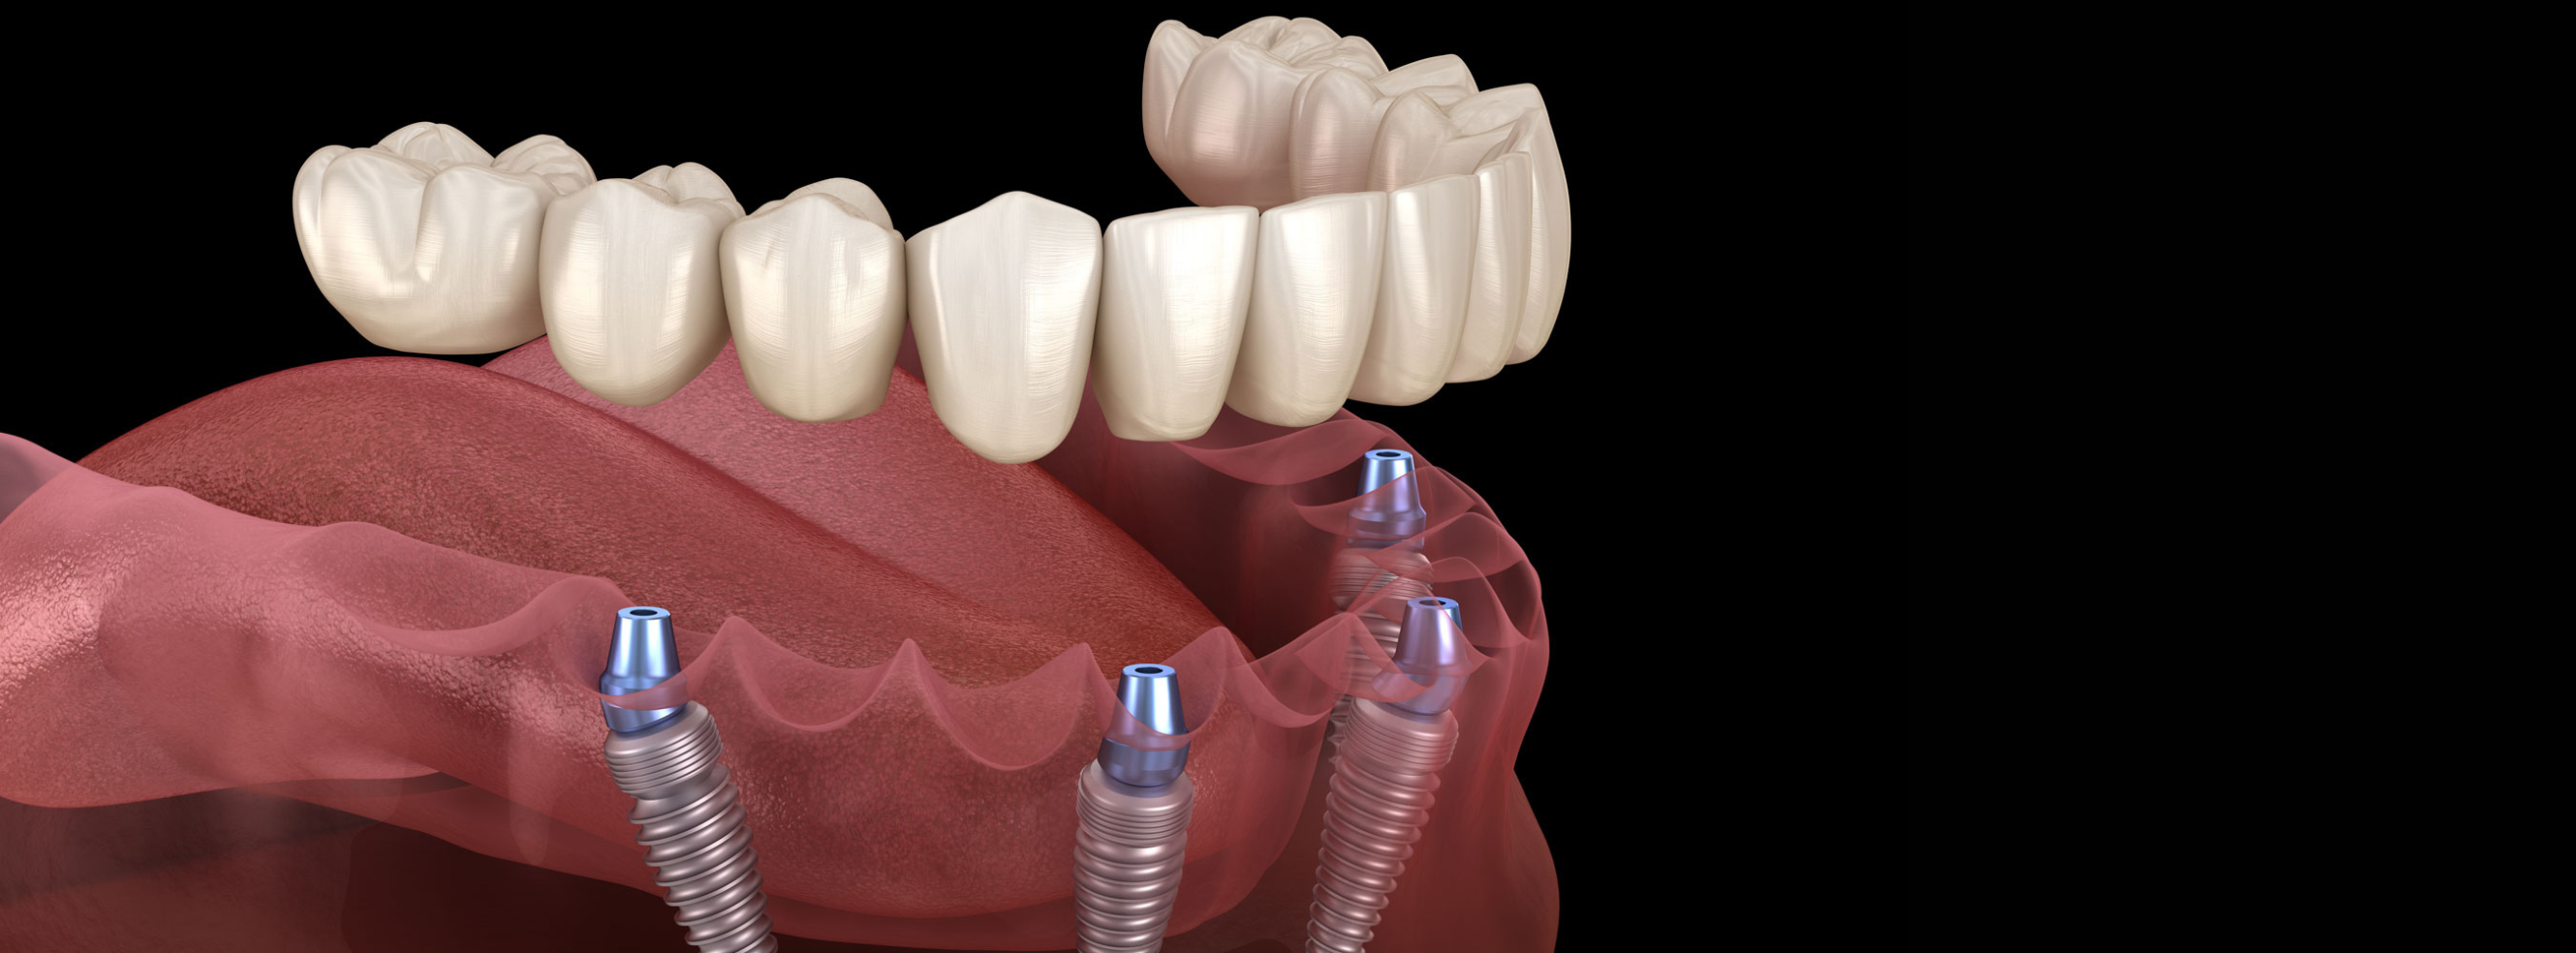

A full-arch dental implant restoration is a life-changing solution for patients who are missing most or all of their teeth, offering a stable, fixed alternative to dentures. Using as few as four to six strategically placed implants, we support an entire upper or lower arch of natural-looking teeth that stay securely in place—no slipping, adhesives, or nightly removal. At National Dental Implant Center of Hauppauge, we use advanced CBCT imaging, digital planning, and guided surgical techniques to ensure each implant is positioned with exceptional accuracy for long-term success. This modern full-arch approach restores full chewing ability, enhances facial support, and delivers a confident, functional smile that looks and feels completely natural.

Single implants replace one missing tooth, implant bridges replace several missing teeth using multiple implants, and All-on-X is a full-arch solution that restores an entire upper or lower set of teeth using as few as four implants.